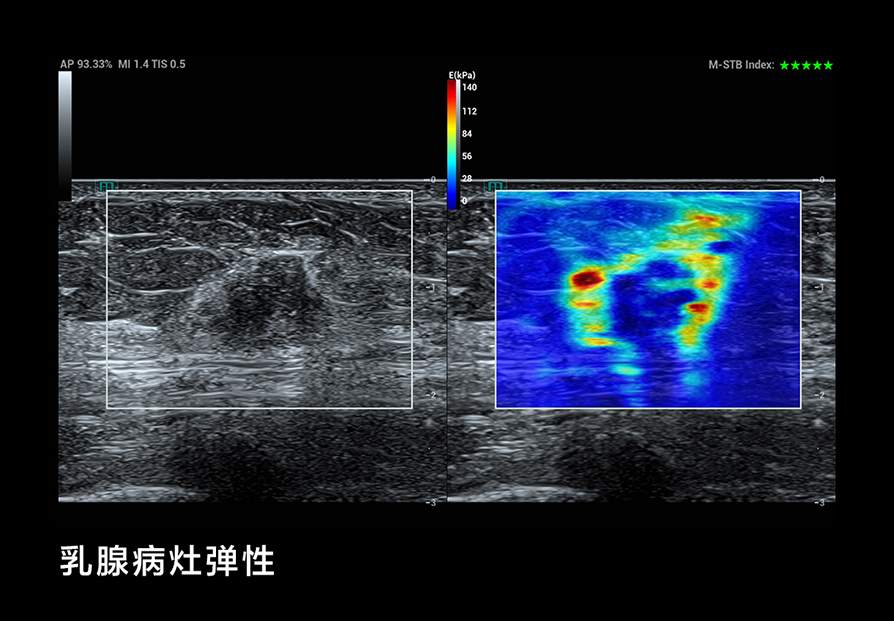

我们在 B-Mode 成像方面考虑了更细(超高频率)、更深(超低频率),更好的对比分辨率,如个异化的 HD Scope,以提高早期鉴别诊断的能力;在超微血流方面, UMA突破传统彩色多普勒的限制,使细微血流的显示达到新的高度;还有创新的血流流变学(VFM)等分析技术,以及流变学与生物力学结合的技术等;在弹性成像方面,我们也有很多可圈可点的地方。我们可以形成多模态,多模式的成像与显示,为临床和科研提供新的工具;在造影成像(CEUS)方面,我们还有极具特色的高帧率造影技术和 CEUS QI 分析系统,还有光声成像等这些新的方向。

我们还用了一个技术,在医院里看到乳腺病灶类的微钙化灶,这些极小的微钙化灶,原来超声是看不见的,只有钼靶才能看到。但能看见微钙化灶对乳腺癌的早期鉴别诊断至关重要。钼靶在乳腺微钙化灶方面有非常细的分类,对早期鉴别诊断提供了非常有意义的指导作用。如果我们持续发展这个超声技术,把它用在日常的临床工作中,那医生就能够更早地发现乳腺病灶的早期微钙化。